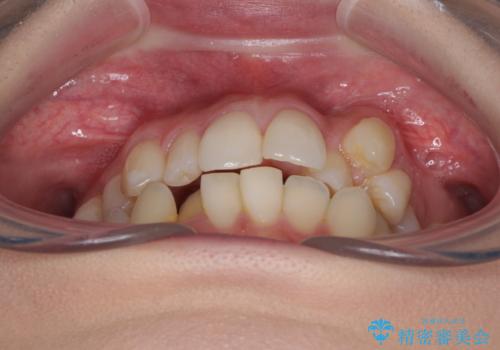

補助装置を併用したインビザラインでの八重歯の抜歯矯正

- 八重歯と奥歯の咬み合わせを気にして来院された患者様です。

インビザラインによる矯正治療を希望されたため、八重歯改善のための抜歯矯正部分は補助装置を併用し、その後はインビザラインにて行うこととしました。

下顎の右側変位が顕著であったため、ワイヤー矯正の方が咬み合わせは改善しやすいのですが、ある程度は時間がかかっても良いとのことであったので、インビザラインにて矯正治療を行うこととしました。